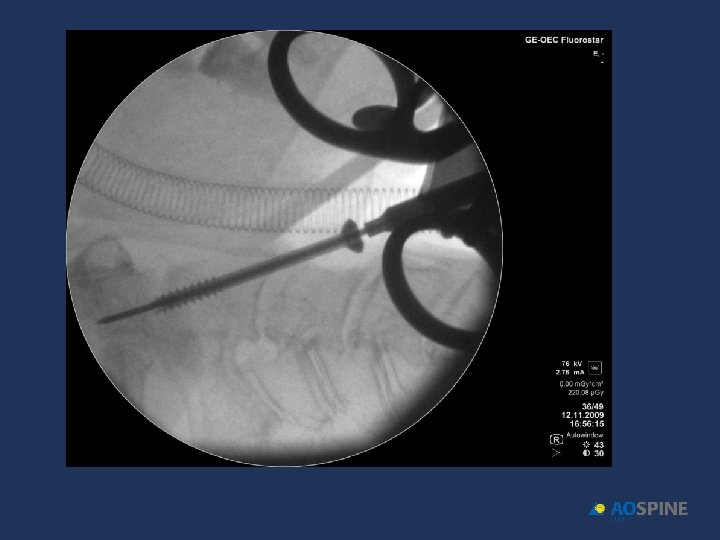

ODONTOID FRACTURES odontoid screw ADVANTAGES CONTRAINDICATIONS • PRESERVES MOTION C 1 C 2 • TRANSVERSE LIG RUPTURE • DONT NEED POSTOP HALO • EXTENSE C 2 BODY FX • DONT NEED BONE GRAFT • IRREDUCTIBLE FRACTURE • ANTERIOR OBLICUE FX

ODONTOID FRACTURES • RIGID COLLAR 10 -12 WEEKS • ONE SCREW • BEST RESULTS DURING FIRST 6 MONTHS AFTER FX Jenkins et al. J Neurosurg 1988, 89 Apfelbaum et al. J Neurosurg 2002, 93

ODONTOID FRACTURES odontoid screw • 90% FUSION TYPE II • 95% FUSION TYPE II < 6 MONTHS EVOL. • 100% FUSION TYPE III